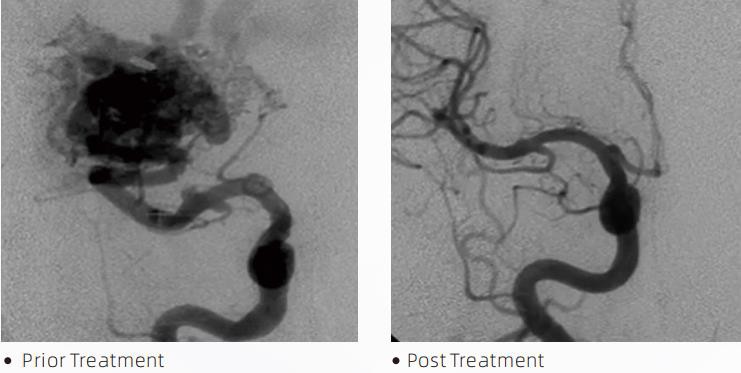

لاواٹی ایممائع ایمبولک سسٹم دماغی خرابی کے علاج کے لئے ایک انٹروینشنل اینڈواسکولر تھراپی ہے۔ Cerebrovascular malformation سے مراد سومی یا مہلک نیوروواسکولر اسامانیتاوں کا ایک گروپ ہے جو انٹراکرینیل ہیمرج، دماغی انفکشن، دماغی اسکیمیا اور دیگر بیماریوں کا باعث بن سکتا ہے۔ مائع ایمبولائزیشن سسٹم ایک طبی آلہ ہے جس کا انتظام سادہ انٹراواسکولر اندراج کے ذریعے کیا جاتا ہے، جو ایک خاص سیال مواد کو انجیکشن لگا کر غیر معمولی دماغی خون کی نالیوں کو ابھارتا ہے۔ سیال مواد خون کی نالیوں کے اندر ایک کنٹرول ٹشو ایمبولزم بناتا ہے، جو مریضوں پر دماغی خرابی کے اثرات کو کم کر سکتا ہے۔ ایک DMSO ہم آہنگ ڈیلیوری مائیکرو کیتھیٹر جو نیوروواسکولیچر میں استعمال کے لیے اشارہ کیا جاتا ہے اس کا استعمال ایمبولائزیشن سائٹ تک رسائی کے لیے کیا جاتا ہے۔ لاوا مائع ایمبولک ایجنٹ ایک غیر چپکنے والا مائع ایمبولک ایجنٹ سسٹم ہے جو DMSO (ڈائمتھائل سلفوکسائیڈ) میں تحلیل شدہ EVOH (ایتھیلین ونائل الکحل) کوپولیمر پر مشتمل ہے، اور فلوروسکوپی کے تحت تصور کے لیے کنٹراسٹ فراہم کرنے کے لیے مائیکرونائزڈ ٹینٹلم پاؤڈر معطل ہے۔ لاواٹی ایمتین پروڈکٹ فارمولیشنز، LAVA-12، LAVA-18 اور LAVA-34 میں دستیاب ہے۔ لاوا-12: ڈسٹل مائیکرو ویسلز اور چھوٹے فیڈرز کے ذریعے کھانا کھلاتے وقت تجویز کیا جاتا ہے۔ لاوا-18: تجویز کیا جاتا ہے جب پیڈیکل انجیکشن کو کھانا کھلاتے وقت نائیڈس کے قریب لگایا جائے گا۔ لاوا-34: اونچے بہاؤ اور بڑے ناسور والے اجزاء کو ابھارنے کے لیے تجویز کیا جاتا ہے۔